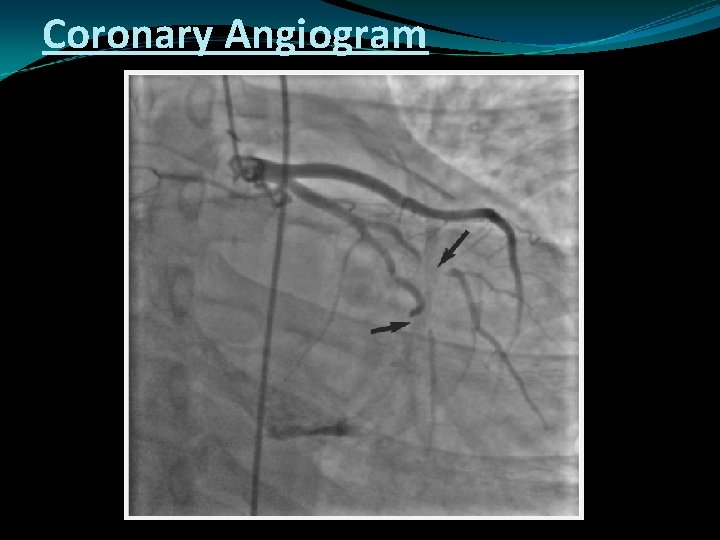

Other Cath. And Coronary Angiogram Features

Coronary Angiogram